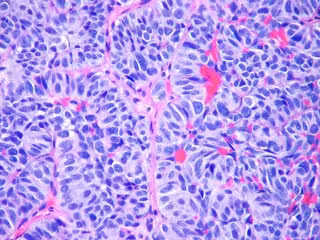

Investigadores identifican cuatro características de la metástasis del cáncer

FLICKR/PULMONARY PATHOLOGY/ CC BY-SA 2.0 - Archivo